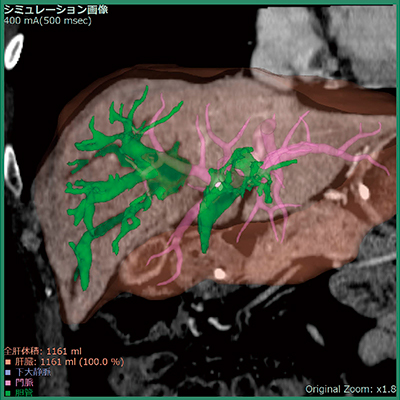

そこでV5.3では,肝内の拡張胆管症例において自動で胆管領域を抽出する機能を実装した(図2)。本機能により,上記問題点が少しでも改善されることを期待する。

また,肝臓解析(CT)では,ディープラーニングを用いて設計した肝臓領域抽出を実装した(図3)。一般的に,ディープラーニング技術では,画像解析の分野において何を特徴とすべきかをコンピュータが自動的に学習できることが特徴であり(従来はソフトウエア開発者が画像の特徴を手動で設計),ディープラーニングが医用画像のポストプロセッシングに用いられることに対する期待は非常に高い。肝臓以外の臓器抽出エンジンにおいても,随時改良を進めていきたいと考えている。なお,VINCENTは臨床現場で学習することはない。

図2 自動抽出した胆管領域の結果画像例

図3 自動抽出された肝臓領域(緑色)